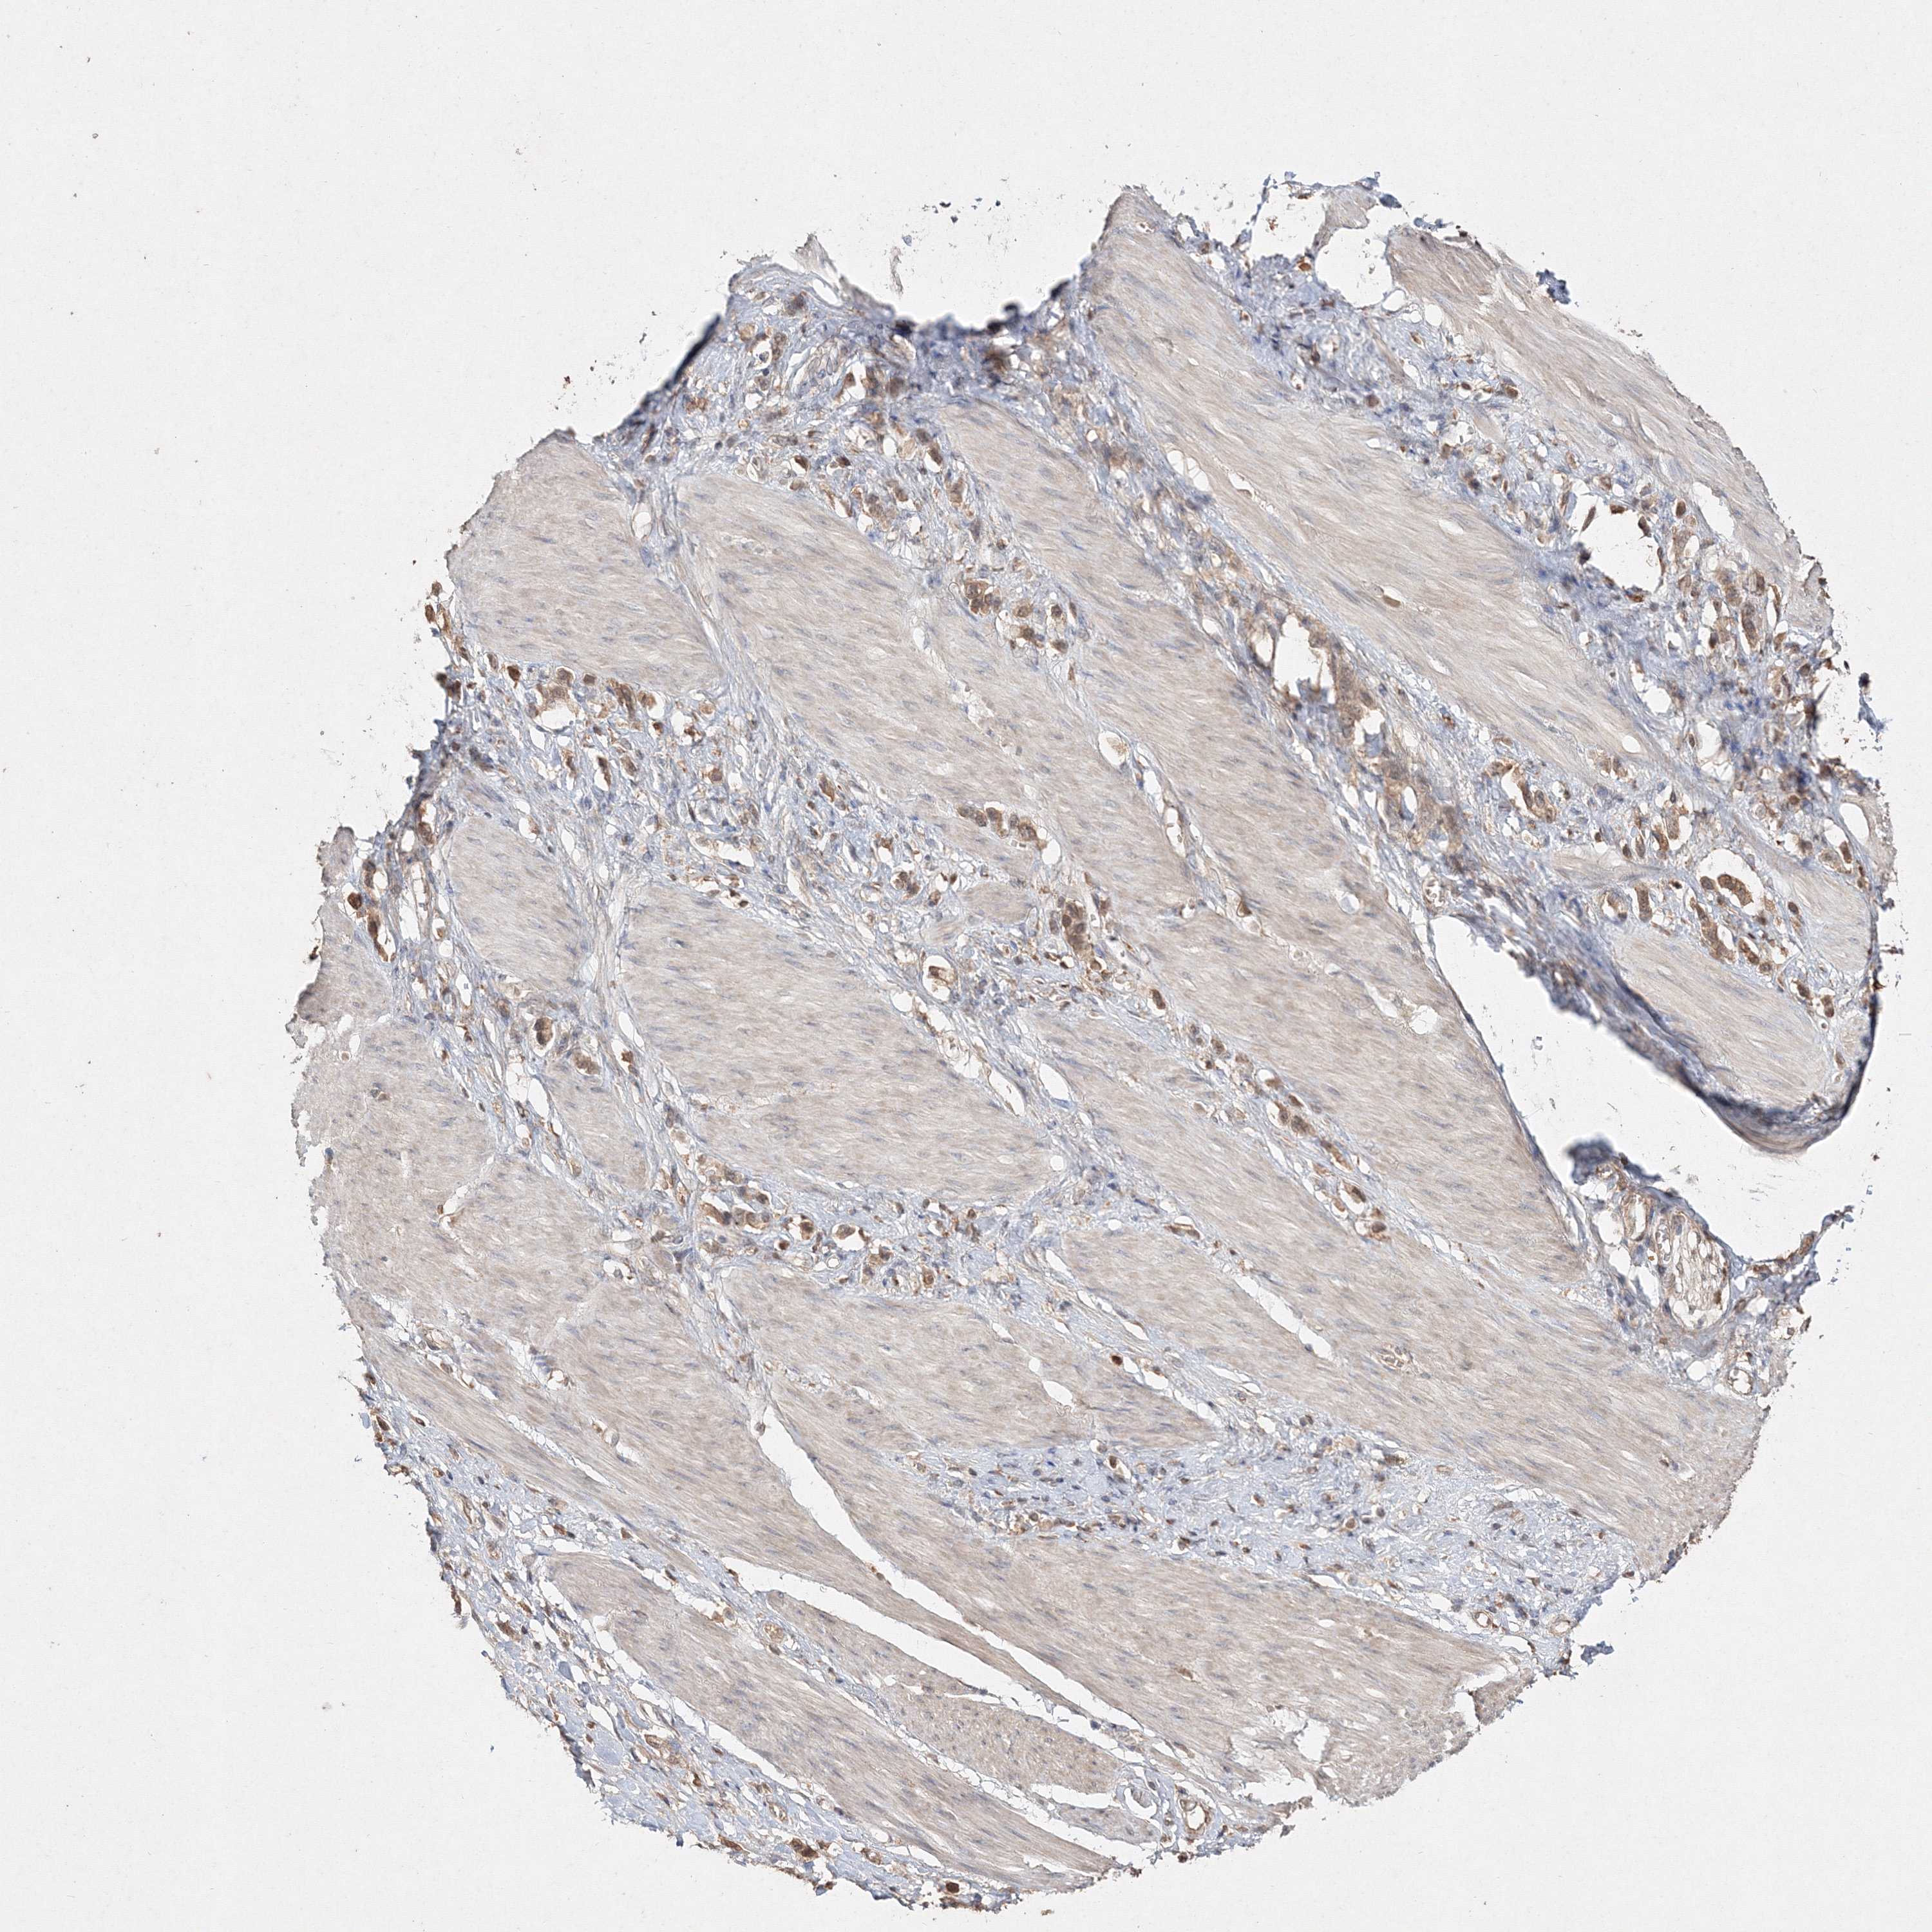

STOMACH CANCER - Protein expressioni

A mouse-over function shows sample information and annotation data. Click on an image to view it in a full screen mode. Samples can be filtered based on level of antibody staining by selecting one or several of the following categories: high, medium, low and not detected. The assay and annotation is described here.

Note that samples used for immunohistochemistry by the Human Protein Atlas do not correspond to samples in the TCGA dataset.

Antibody stainingi

Antibody staining in the annotated cell types in the current human tissue is reported as not detected, low, medium, or high, based on conventional immunohistochemistry profiling in selected tissues. This score is based on the combination of the staining intensity and fraction of stained cells.

Each image is clickable and will lead to virtual microscopy that enables deeper exploration of all samples and also displays staining intensity scores, fraction scores and subcellular localization as well as patient and tissue information for each sample.

Antibody HPA042745

Antibody CAB034320

Staining

High

Medium

Low

Not detected

Intensity

Strong

Moderate

Weak

Negative

Quantity

>75%

75%-25%

<25%

None

Location

Nuclear

Cytoplasmic/membranous

Cytoplasmic/membranous,nuclear

Adenocarcinoma, NOS